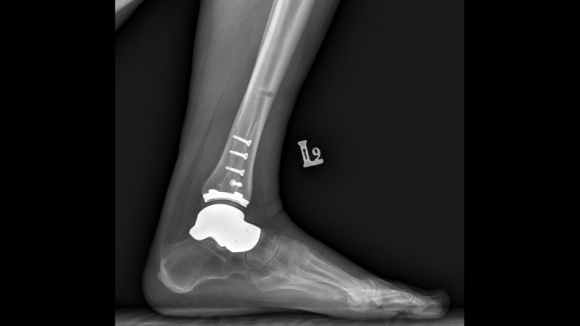

Jesienią odbyły się pierwsze w Polsce (i jedne z pierwszych w Europie) innowacyjne operacje stawu skokowego z wykorzystaniem hybrydowego wszczepu. Ich istotą było połączenie implantu kości skokowej z endoprotezą stawu skokowego. To rozwiązanie dla pacjentów z dużym uszkodzeniem kości skokowej.

Nowa proteza składa się z indywidualnie wykonanego, ?szytego na miarę? implantu kości skokowej, który zastępuje blokującą ruch w stawie skokowym i podskokowym zniszczoną kość skokową, oraz połączonego z nim elementu piszczelowego protezy stawu skokowego. W takim zestawieniu obie protezy tworzą wszczep hybrydowy, pozwalający na przywrócenie prawidłowego ruchu w stawie.

? Implant hybrydowy, zastępujący staw i całą kość skokową, nie był dotychczas stosowany w Polsce ? mówi lek. Andrzej Komor, ortopeda z kliniki Carolina Medical Center, który wykonał pierwsze operacje. ? Kość skokowa to kluczowy element mechanizmu stopy i stawu skokowego. Jeśli jest uszkodzona, staw przestaje funkcjonować. W sytuacji, gry zmiany zwyrodnieniowe dotyczą wyłącznie powierzchni stawowej kości, wykonywana jest standardowa procedura endoprotezoplastyki. Natomiast w przypadku, kiedy uszkodzona jest duża część kości, należy usztywnić cały staw lub zastąpić zniszczoną kość i staw implantami.

? Gdy kość jest zniszczona i nie można jej odwzorować bezpośrednio, wówczas punktem odniesienia jest ta sama kość z drugiej kończyny, a właściwie jej lustrzane odbicie. Trzeba jeszcze pamiętać, że nowa kość musi idealnie pasować do pozostałych kości stopy: piętowej, łódkowatej, klinowatej ? mówi lek. Andrzej Komor. ? Aby tego dokonać, robimy tomografię komputerową obu stawów. Na podstawie tomografii wykonywane są wydruki 3D zniszczonej kości oraz zdrowego stawu drugiej nogi. Wtedy przychodzi faza dopasowywania do stawu i kalibracji wymiarów ? w całym procesie korzystamy ze specjalnego programu komputerowego.